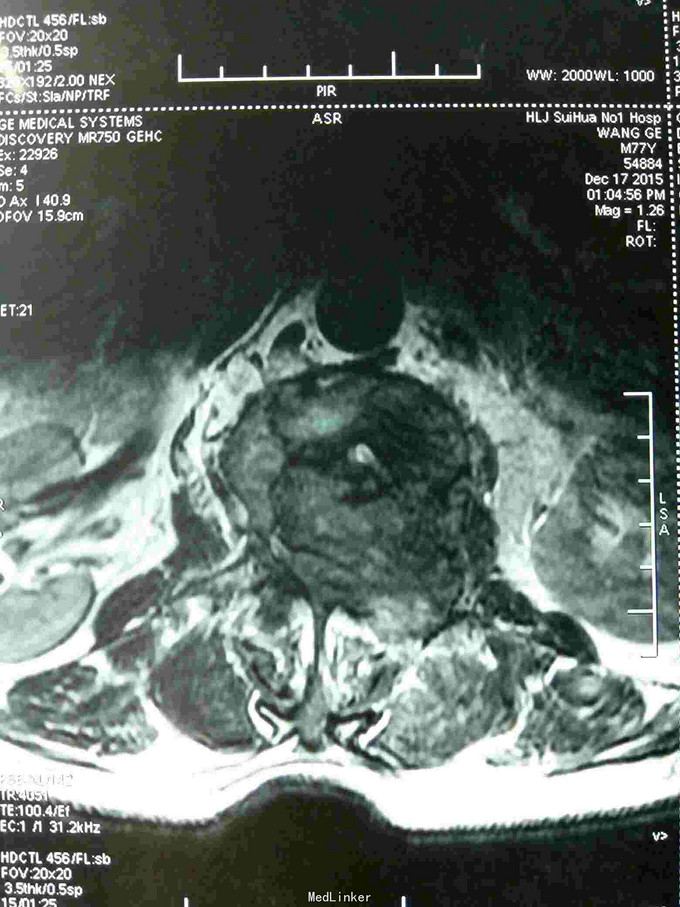

根据病史查体诊断:腰间盘突出症待确诊。应用消肿营养神经镇痛治疗。一天。查核磁共振示:腰椎多节段间盘突出伴椎管狭窄。第二腰椎骨破坏侵及椎板。部分突入椎管,脊髓受压。诊断:腰间盘突出伴椎管狭窄。第二腰椎转移癌,脊髓受压。经与家属沟通,查双肺CT:双肺下叶炎症。肺部纤维化。可见肿瘤阴影。肋骨及胸膜受累。胸椎部分骨破坏。最终诊断:双肺癌,胸椎,腰椎骨转移,脊髓受压。多节段腰椎间盘突出。病人至肿瘤科治疗。